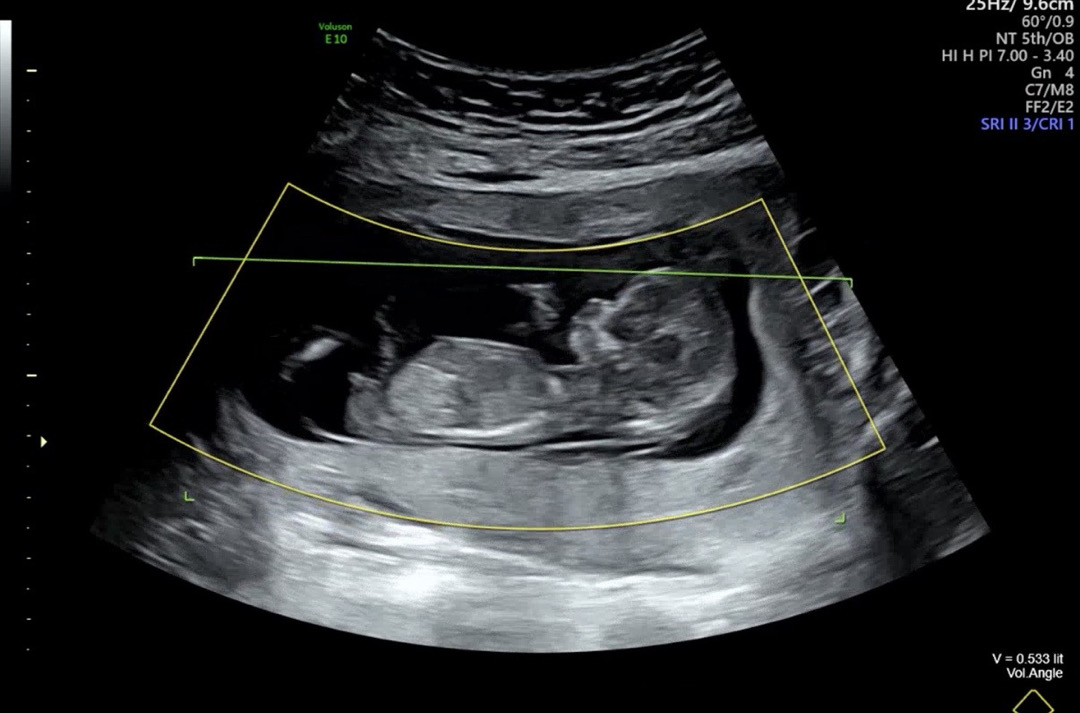

12주2일 각도법좀 봐주세요~~

둘째라 그런가 더 궁금하네요 !! 고수님들 한번 봐주세요!